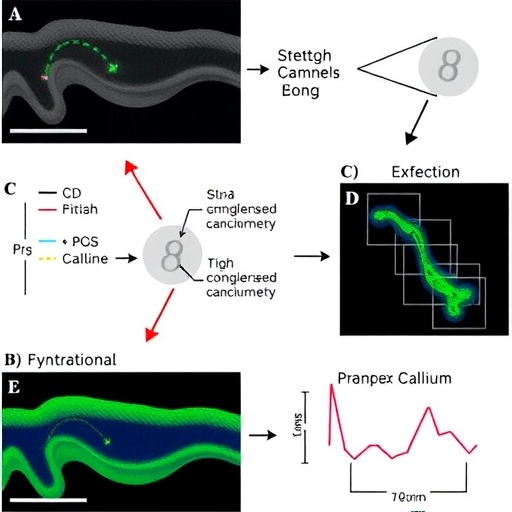

Using cutting-edge molecular biology techniques and functional assays on human ASM cells isolated from developing lungs, the researchers meticulously examined the expression pattern and activation profile of Piezo channels in response to controlled mechanical stretch. Their data revealed that exposing ASM cells to a physiologically relevant stretch stimulus robustly activated Piezo-mediated calcium influx. This activation was finely tuned, meaning that partial stretch induced moderate calcium entry, whereas sustained or excessive stretch drove higher influx, suggesting a graded response suitable for nuanced control of ASM function.

Crucially, the study also explored the relationship between Piezo channel activation and store-operated calcium entry (SOCE), a well-known calcium entry mechanism triggered by the depletion of calcium stores within the endoplasmic reticulum. SOCE involves the coordinated action of STIM and Orai proteins to replenish intracellular calcium, maintaining cellular calcium homeostasis and function. The researchers found a novel crosstalk wherein stretch-induced activation of Piezo channels modulated SOCE activity in developing human ASM cells. This unexpected link underscores a complex signaling network integrating mechanical stimuli with intracellular calcium regulation.

Further investigations showed that blocking Piezo channels pharmacologically or via gene silencing disrupted the normal calcium signaling pattern in response to stretch. This disruption led to diminished SOCE and altered ASM contractility, implying that Piezo channels are indispensable for proper mechanotransduction and calcium homeostasis in developing airways. These findings carry profound implications for understanding how airway smooth muscle develops functional properties during prenatal and early postnatal stages.

The experimental design incorporated state-of-the-art calcium imaging, patch-clamp electrophysiology, and molecular interference techniques to rigorously dissect the roles of Piezo and SOCE pathways. High-resolution live-cell imaging demonstrated real-time calcium dynamics in ASM subjected to mechanical stretch, directly linking mechanical inputs with intracellular signaling events. Concurrent electrophysiological recordings validated the ion channel activity corresponding to the observed calcium influx.